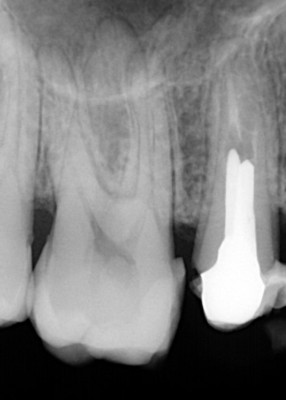

Wskazaniem po takiego leczenia są sytuacje, w których pojawiły się zmiany w okolicy wierzchołków korzeni lub podczas pierwszego leczenia kanałowego kanały zęba zostały opracowane i wypełnione w sposób nieprawidłowy – najczęściej nie zostały dopełnione do wierzchołka korzenia zęba. Obydwa przypadki można zdiagnozować na podstawie analizy obrazu radiologicznego.